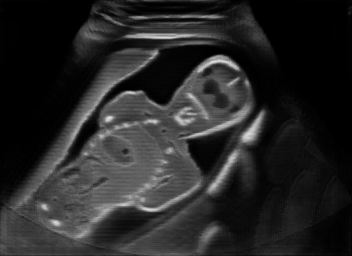

Real in-vivo images. 22 ultrasound sequences were collected using a GE Voluson E8 machine during standard fetal screening exams of 8 patients. Each sequence is several seconds long. We extracted all 4427 frames and resize them to , see Fig. 2 for some examples. The resulting image set was randomly split into training-validation-test sets by a 80-10-10% ratio.